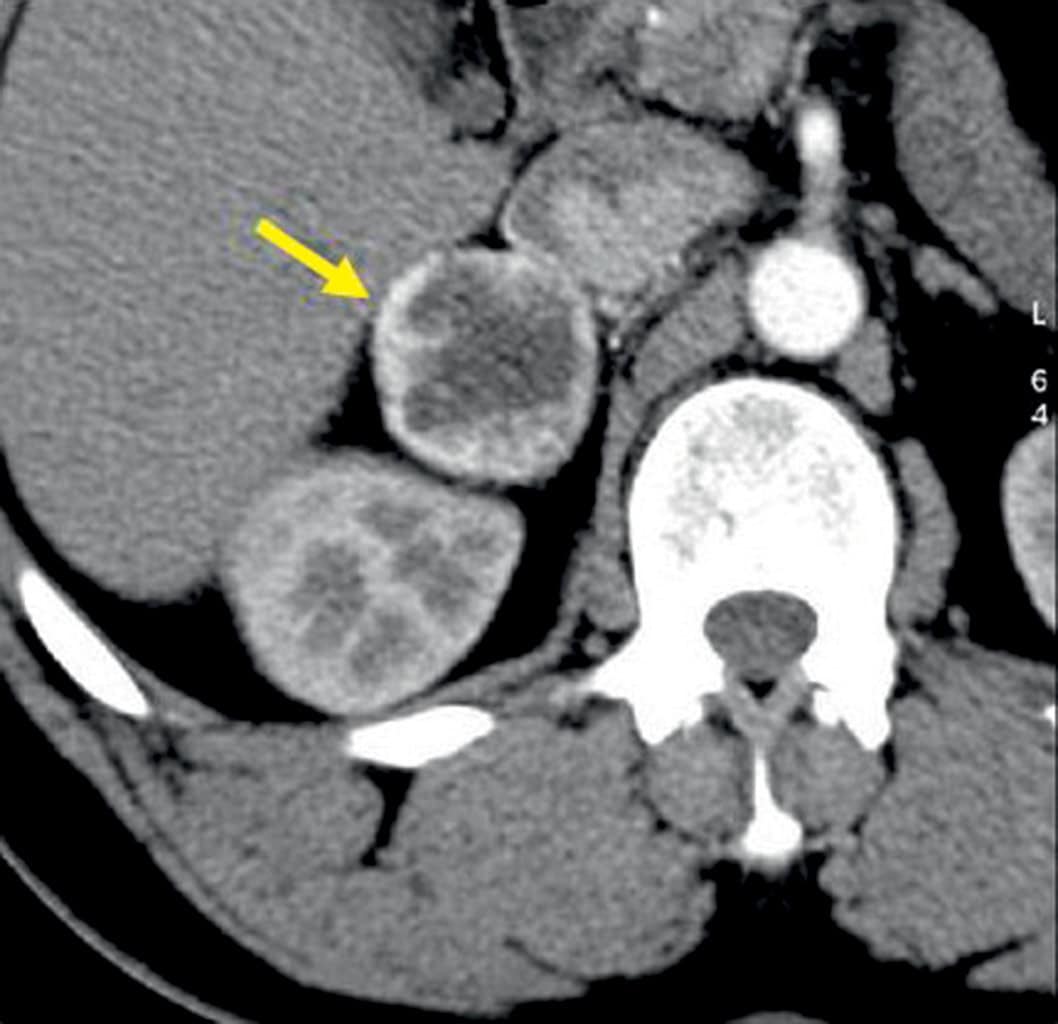

Figure 2.9. Phéochromocytome droit révélé par une HTA sévère chez un homme de 44 ans.

Coupe de scanner abdominal injecté. La masse, nécrotique (niveau liquide visible), se situe dans la loge surrénalienne, en regard du pôle supérieur du rein.